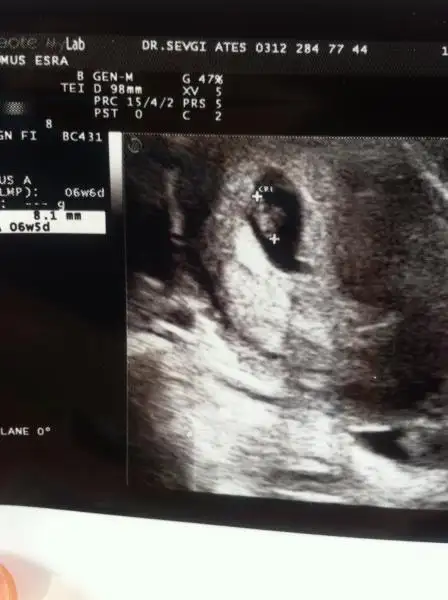

- 30 Nisan 2008

- 45.779

- 24.642

- 398